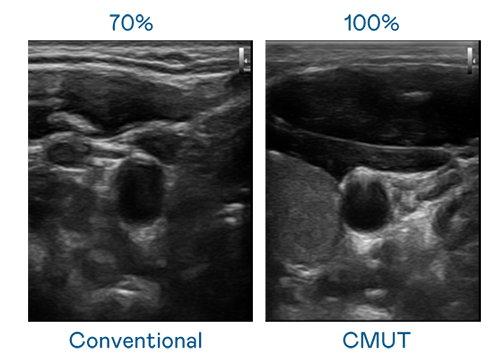

CMUT 技术是一种用电容式微机电元件来产生超音波讯号的技术。与传统 PZT 压电式技术相比,CMUT 频宽增加 30%,更宽频的超音波讯号让影像解析度大幅提升,是实现高影像品质医疗超音波扫描、促进精准医疗发展的关键技术。

大频宽带来超清晰影像

超音波影像的解析度高低,首先取决于探头能发出的讯号频宽。成人看片7777.tv CMUT 可提供高清晰的超音波讯号,提供高频宽、高灵敏度、影像纹理细节更高的超音波影像,协助医护人员缩短影像判读时间及利用精准的医疗影像进行诊断。